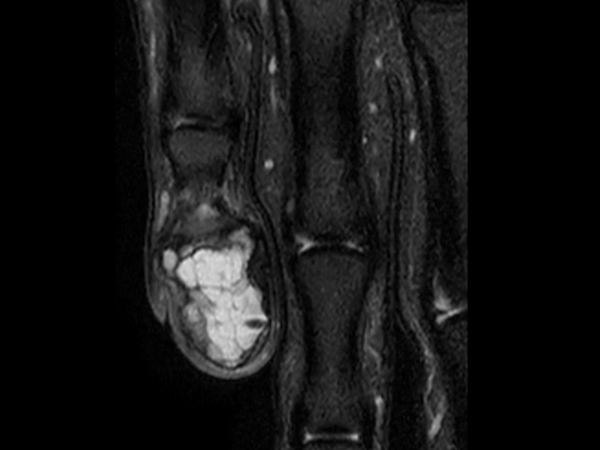

PDw TSE FatSat Compressed SENSE